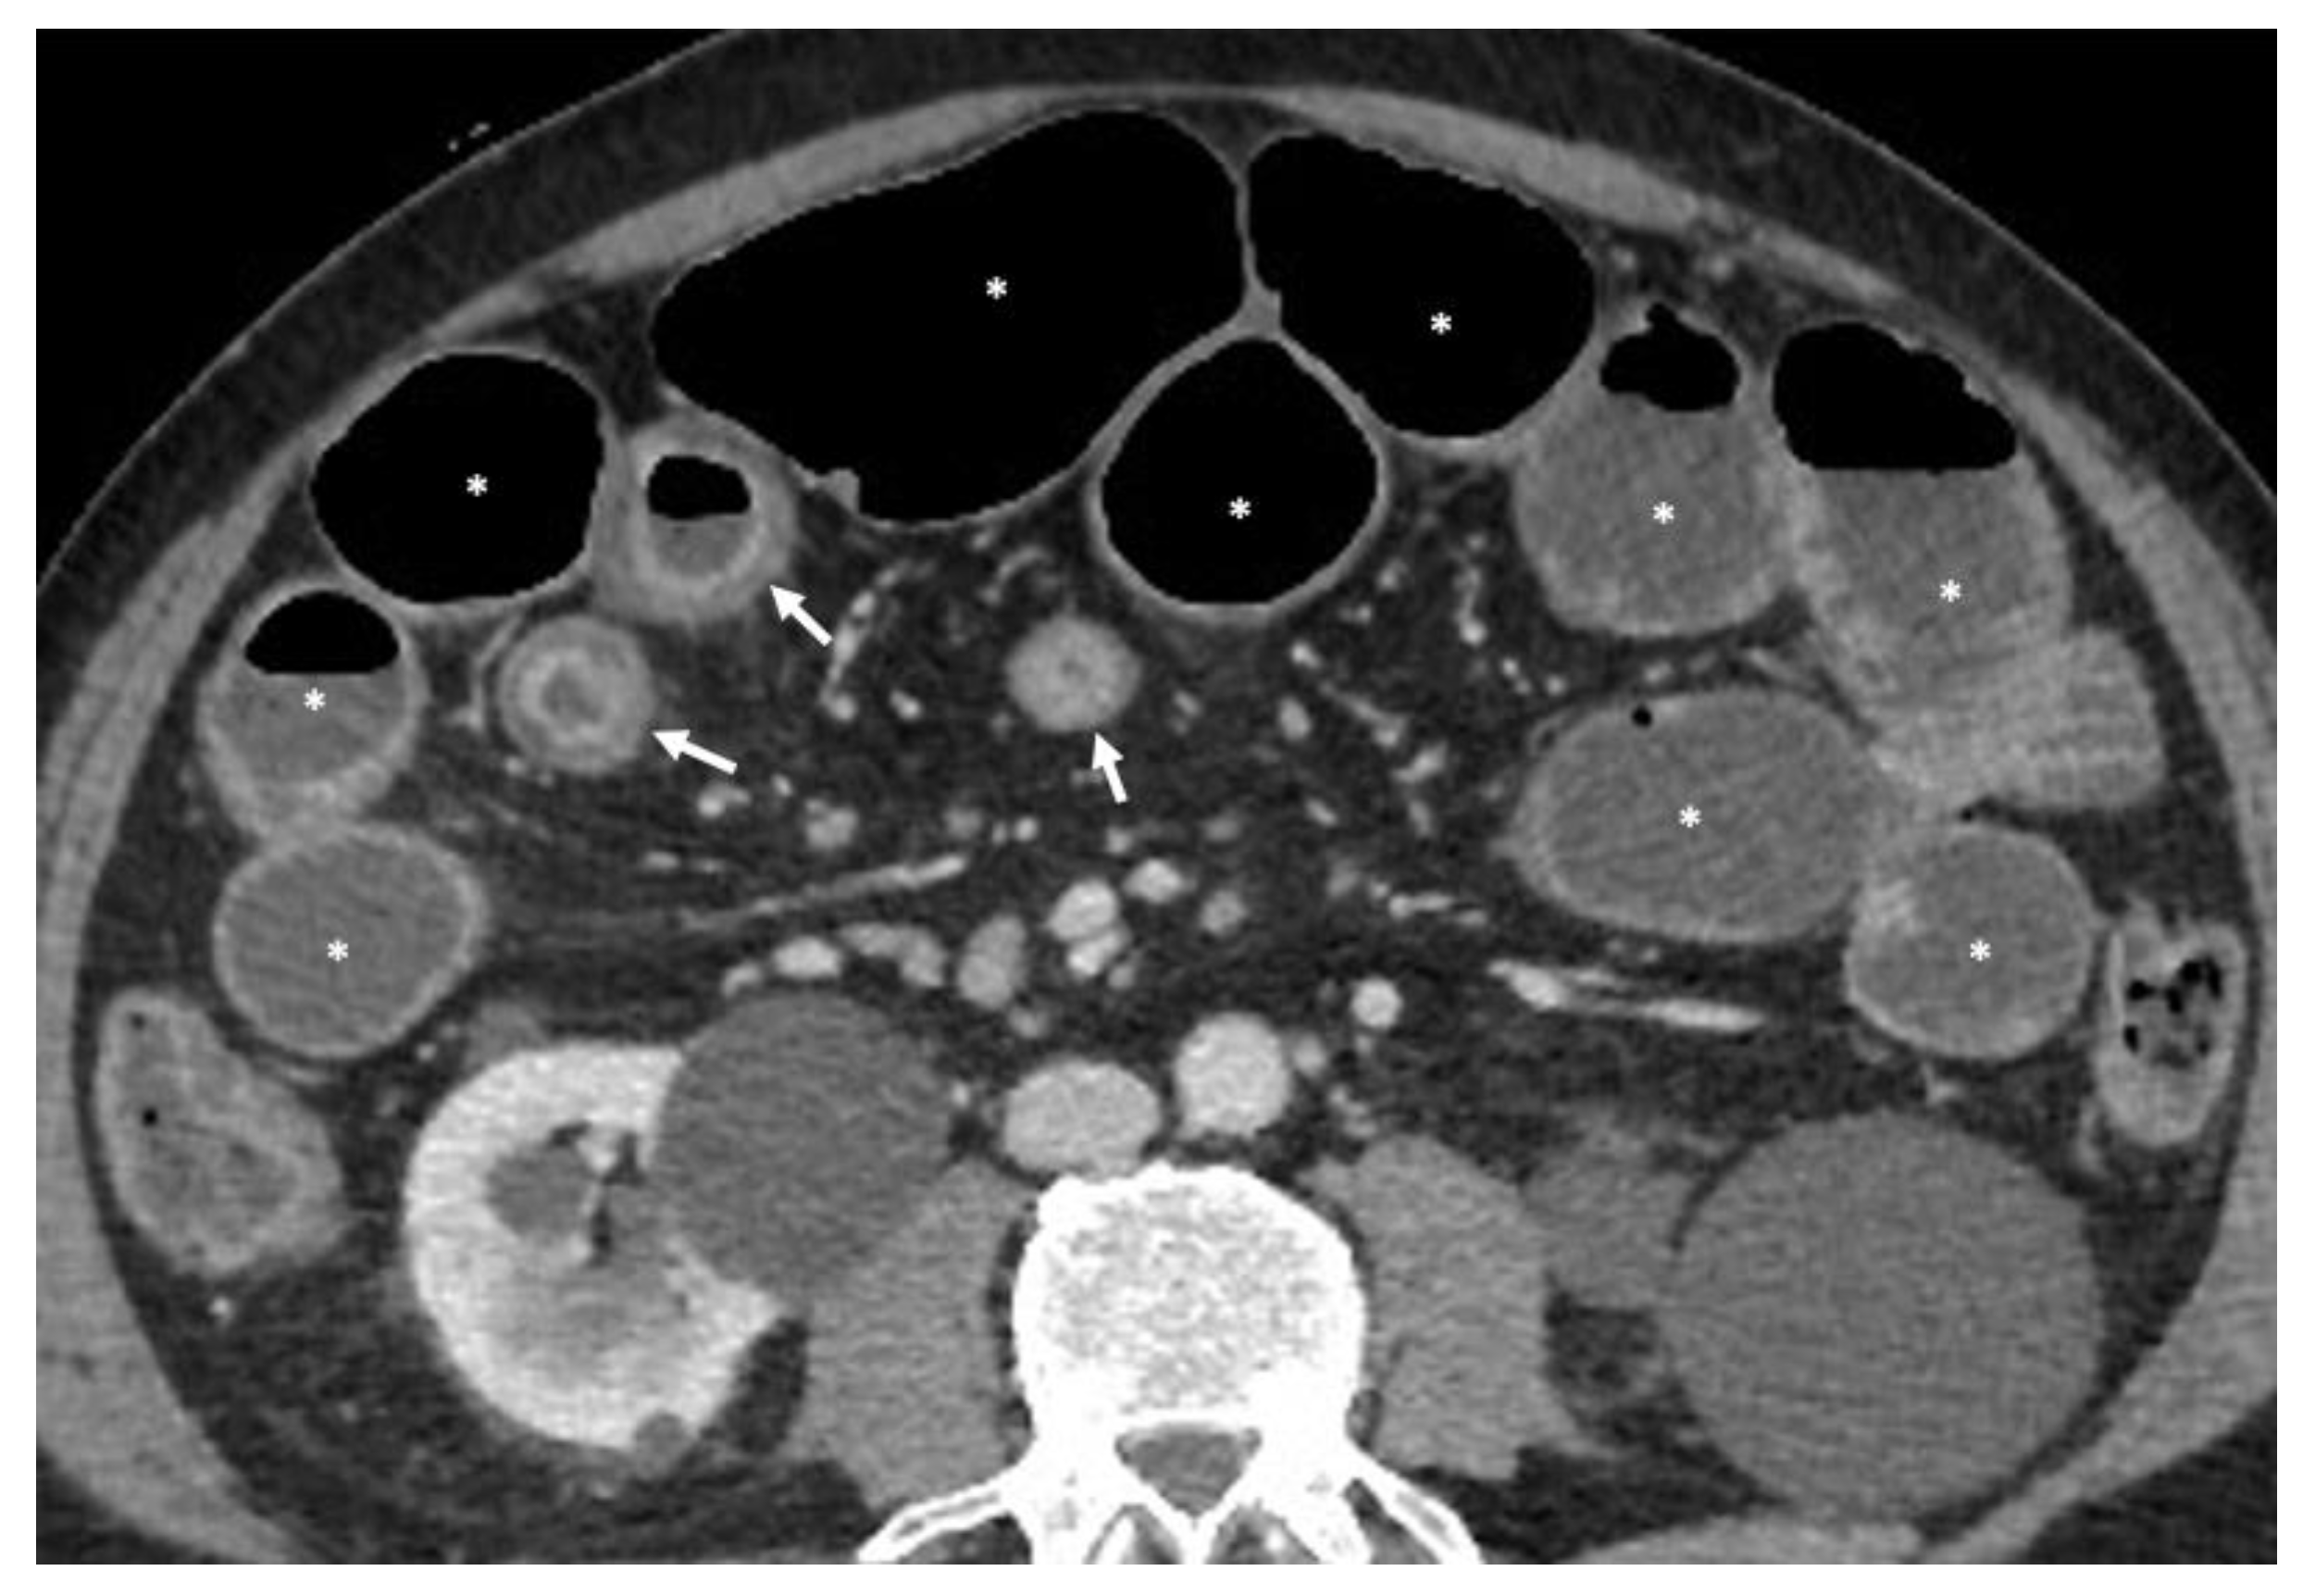

- A normal bowel loop caliber ranges between 2 and 2.5 cm. A bowel lumen is dilated when it has a maximum diameter greater than 2.5–3 cm. The dilation is mild when the upstream lumen is dilated up to 4 cm and severe when it is more than 4 cm (Figure 3) [24]. Pre-stenotic bowel dilatation should always be checked, as it is a sign related to bowel obstruction. Moderate to severe stenosis was determined via double-contrast imaging (conventional barium study) with a sufficient amount of injected air, and stenosis was defined as stenosis in which the lumen was less than one half that of neighboring healthy intestine [25].